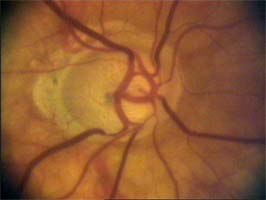

Očekávali byste protažení exkavace k hornímu pólu terče, jak nám ukazuje tento snímek z tomografu HRT II.

exkavace levé oko

Na kterém oku je exkavace větší, na pravém nebo na levém? Podle pohledu na fotografie jistě na levém.

exkavace pravé oko

Na kterém oku je exkavace větší, na pravém nebo na levém? Podle pohledu na fotografie jistě na levém.

Co je příčinou toho, že při pohledu na snímky hodnotíme rozsah exkavace nesprávně? Je to skutečnost, že i růžová oblast neuroretinálního lemu může být již prohloubená, což vídáme zvláště na počátku rozvoje glaukomové neuropathie.

A jak se můžeme vyhnout záměně okrsku bledší barvy za skutečnou exkavaci? Tím, že budeme mít na paměti, že exkavace může být větší než nablednutí. Také zařazení zeleného filtru na pomůže snížit nežádoucí barevný kontrast.